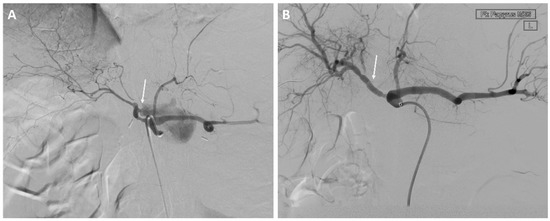

Coiling of the eroded vessels was done in 28 (78%) of the EVT patients and in three (10%) of the OS patients who developed recurrent bleeding. The median number of coils used was seven coils (range, 2–23 coils) see Figure 3.

Figure 3.

A 74-year-old man with a history of cholangiocarcinoma of the extrahepatic bile ducts treated with resection of the bile ducts and biliodigestive anastomosis. (A) Angiography showing bleeding from the right hepatic artery. (B,C) Endovascular coil embolization of the right hepatic artery.